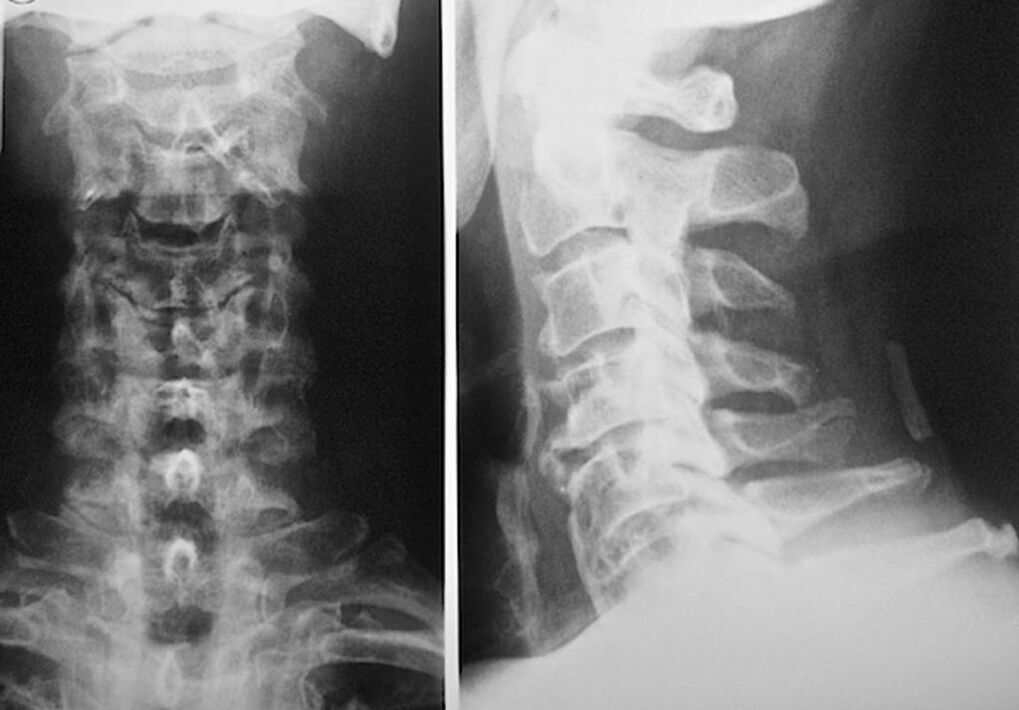

Omurlararası disklerin durumunun teşhisi ve doğru değerlendirilmesi için aşağıdaki araştırma yöntemleri kullanılır:

- Radyografi.

- CT tarama.

- Manyetik tomografi.

- Boyun damarlarının ultrason taraması.

Her biri sağlık için tamamen güvenlidir ve aşırı maruz kalma tehdidi taşımamaktadır. Tedavisi hayatın geri kalanı boyunca yapılacak olan servikal vertebra osteokondrozunun teşhisi, basit bir görsel muayeneden sonra yapılabilir. Herhangi bir ortopedist bunu kolayca yapabilir. Bir istisna, servikal bölgenin görünür patolojileri fark edilmediğinde, hastalığın ilk aşamasıdır.